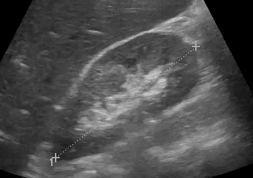

Pathologies des voies urinaires